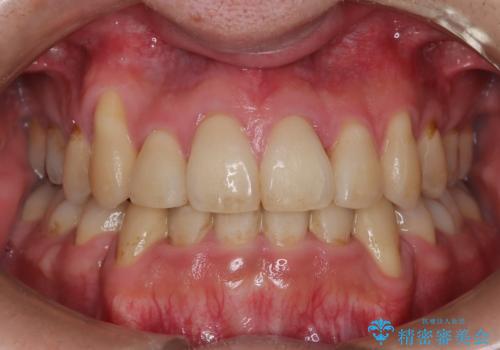

- 以前、上下左右4本抜いてワイヤー矯正をしていた方で、後戻りで下の前歯のガタガタを気にして来院されました。

マウスピース矯正にて、下の歯はIPR(歯と歯の間を削る)を入れることでガタガタの改善、咬み合わせの深さも改善をはかる治療計画をたてました。

歯と歯の間を削って隙間を作って矯正をしています。

保定装置(後戻り防止のための装置)は、基本的にはマウスピースタイプをお渡ししているのですが、患者様のご希望で取り外ししないタイプを希望されたので、前歯の裏側を細いワイヤーで固定(ボンディングリテーナー)を作成しています。